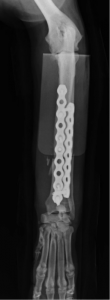

術後レントゲン

コメント;

短い遠位骨片にはφ2.7mmのコルチカルスクリュー1本とφ4.0mmのロッキングスクリュー2本を使用しました。KYON社のALPSプレートはその形状からプレートを並列した場合、骨に対するプレートの幅を他のDCPプレートなどと比較して最小限にすることが可能でありダブルプレートを実施する場合には非常に有効と思われます。